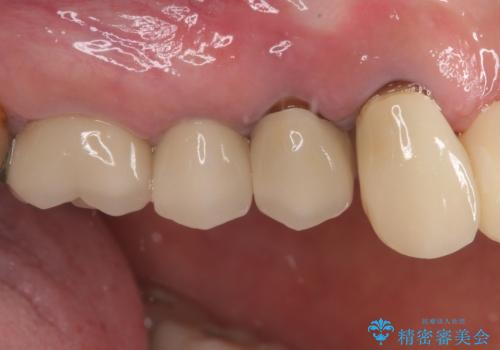

- 歯肉から膿が出てくるのが気になるとのことで来院された患者様です。

診察したところ、歯根に破折線が確認され抜歯が必要な状態でした。

歯肉や歯槽骨の状態は良好であったため、抜歯即時埋入インプラントによる補綴治療を行うこととしました。

膿の出口が認められた頬側の歯槽骨は欠損が大きかったものの、インプラント埋入には十分な骨があり、無事に短期間で治療を終えることができました。